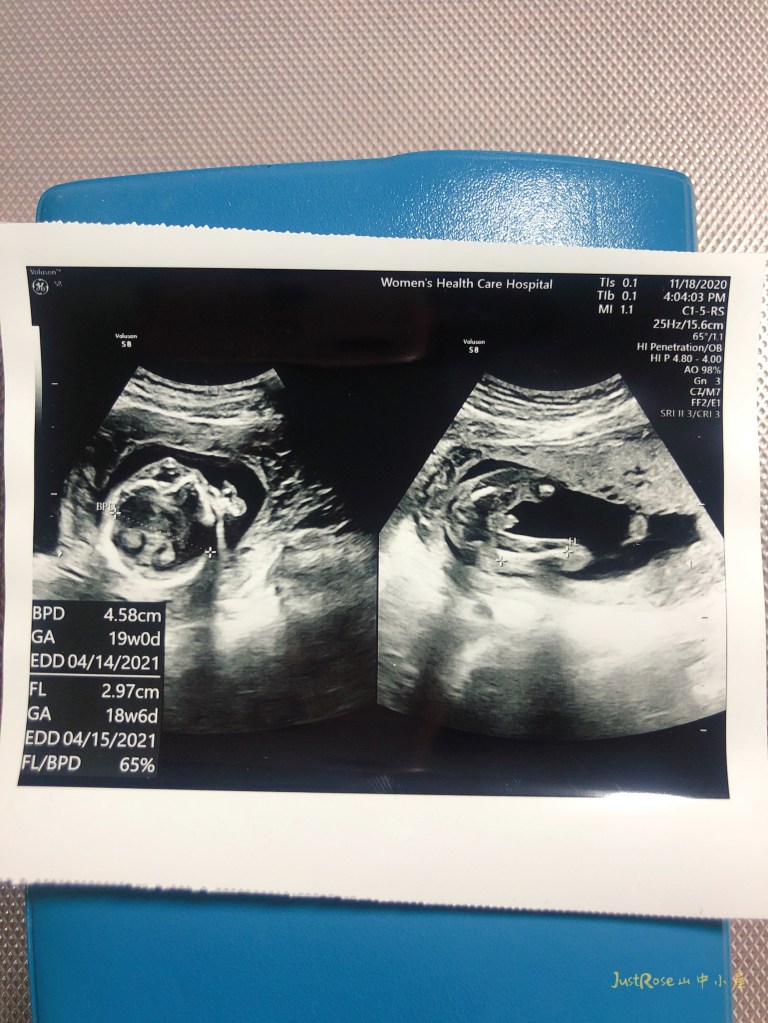

每次去照超音波,都會要求一定要聽一下心跳,甚至初期、中期一個月只要產檢一次,我們夫妻倆都有默契隔兩週就去看他一次。每次聽到醫生說,小朋友很好,頭圍、肚圍、大腿長度都有在他的週數,我們都好開心。離開門診時在車上我們都會摸著藍天誇獎他好棒!

記得有一次,要確認性別時產檢的前一晚(我們在前幾週就已經大概知道性別),我也是跟他說明天醫生阿公會幫你照超音波,你的腳要開開一下,動一下,讓媽媽知道你的性別喔,隔天一照超音波馬上照到,之後每次都照到…溝通還真有效。他的活動力很好,除了有一次他應該在睡覺,其他的時候動作都很多,有時候瘋狂的揮手、伸腳,最近醫生開到3D,我們看到他的五官,他在微笑。(18週,在20週以上五官會更明顯)